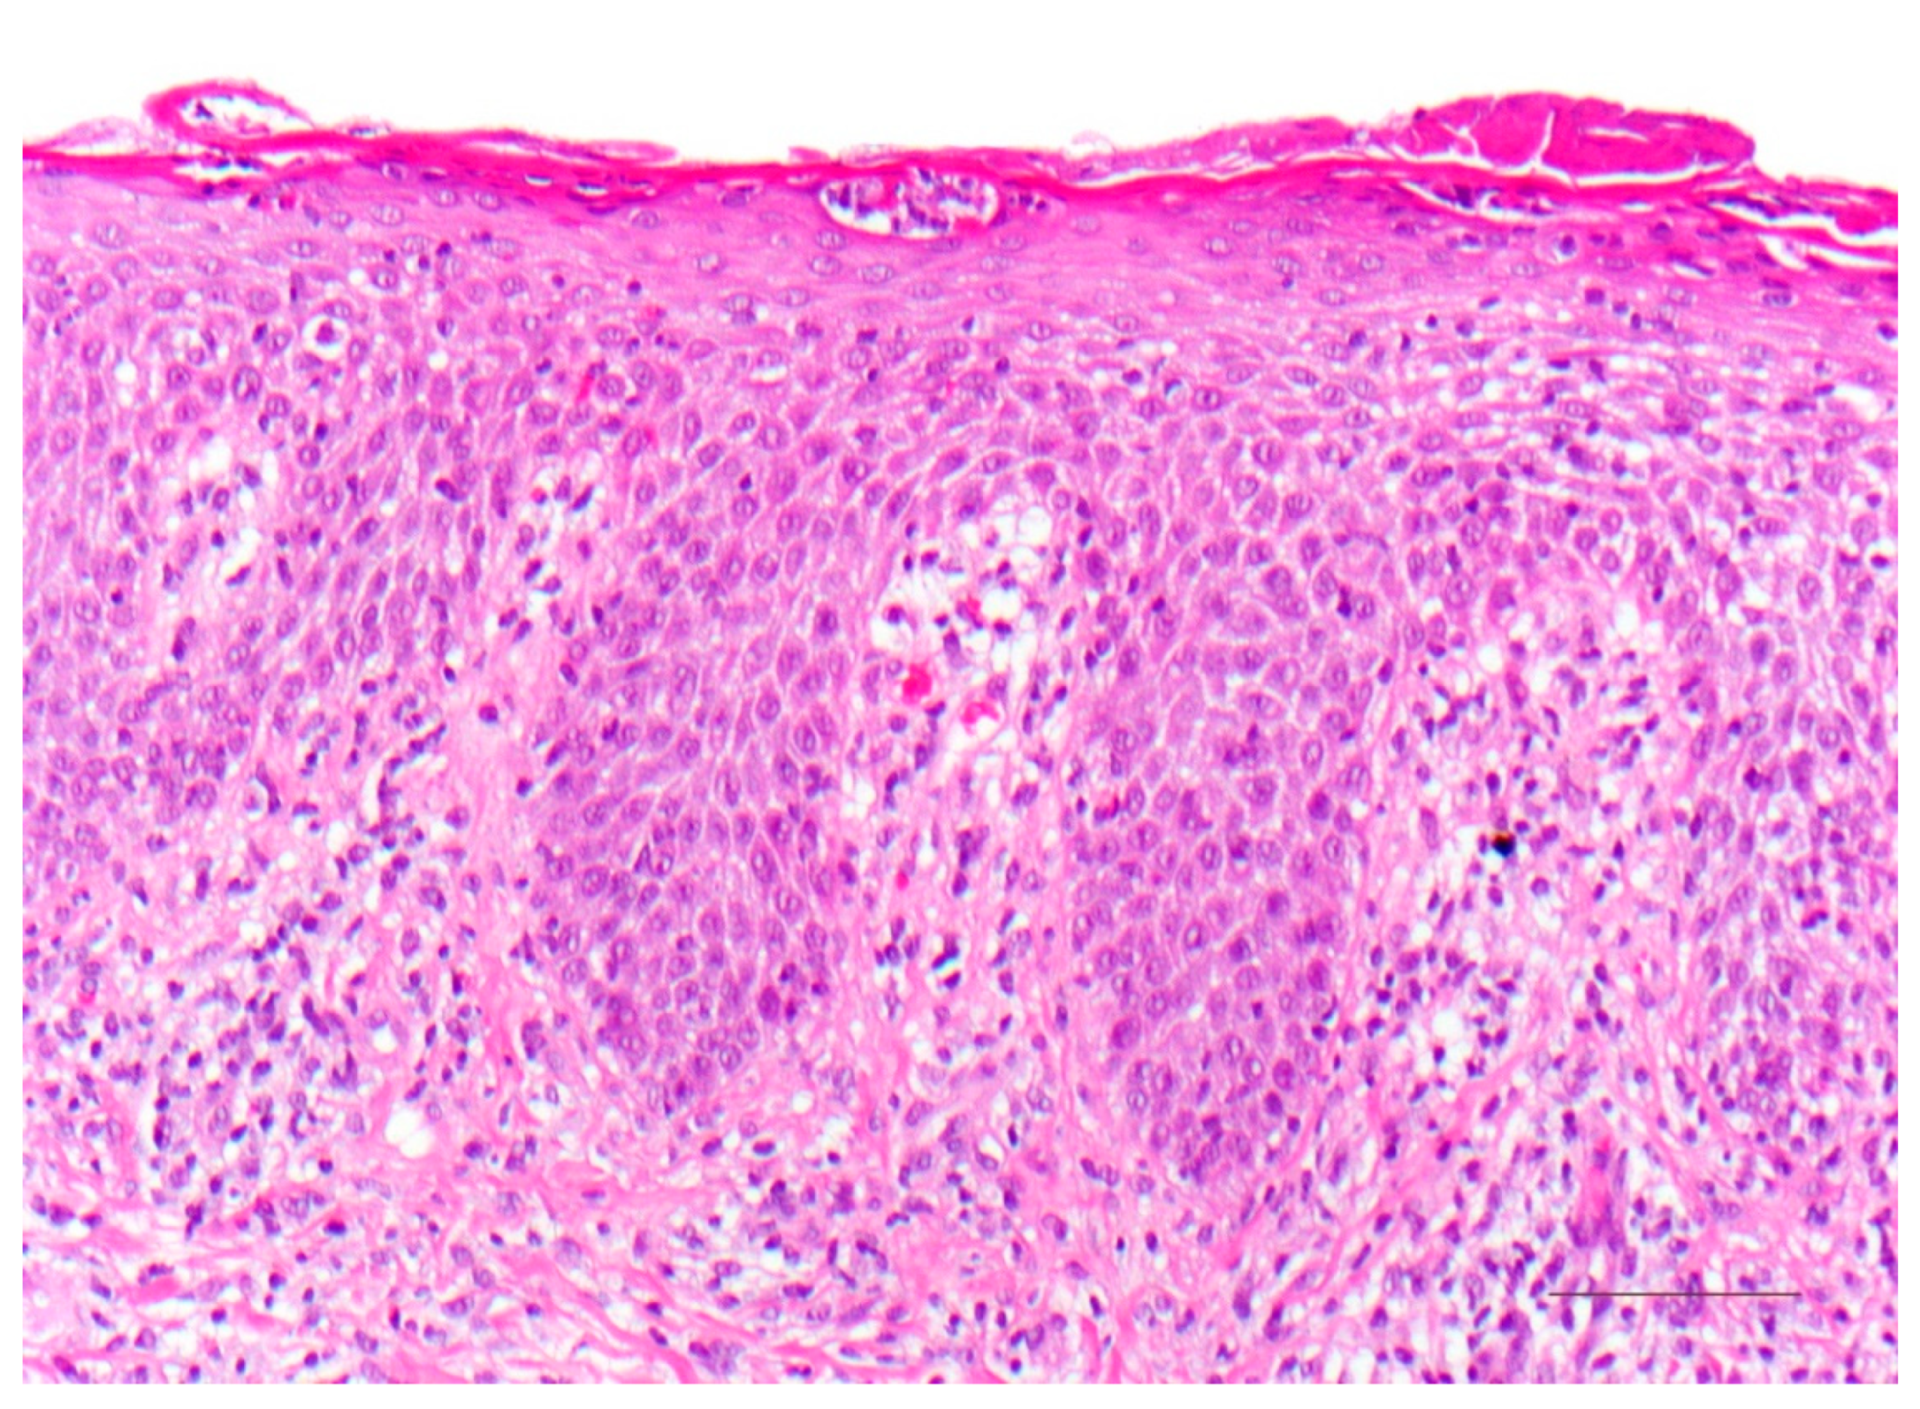

Ichthyosen umfassen eine heterogene Gruppe seltener hereditärer Hauterkrankungen, deren Klassifizierung sich als schwierig erweisen kann. Dementsprechend ist eine schnelle Diagnosefindung und Therapieeinleitung im klinischen Alltag eine Herausforderung. Auf Genodermatosen spezialisierte Experten der Klinik für Hautkrankheiten am Universitätsklinikum Münster haben in einem Überblicksartikel dermatopathologische Merkmale verschiedener Ichthyose-Subtypen zusammengefasst. Der Review erschien in der Fachzeitschrift Dermatopathology.